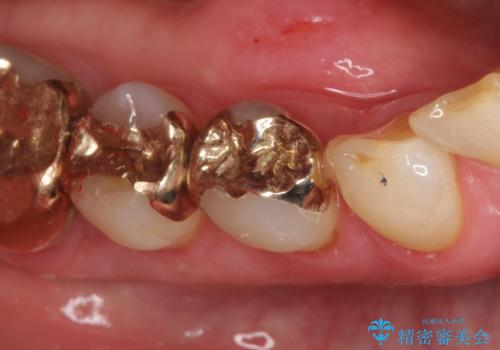

PGAインレーにて修復治療を行いました。

ゴールドインレーは適合が良く、割れることもないため、長期的に安定した治療法となります。